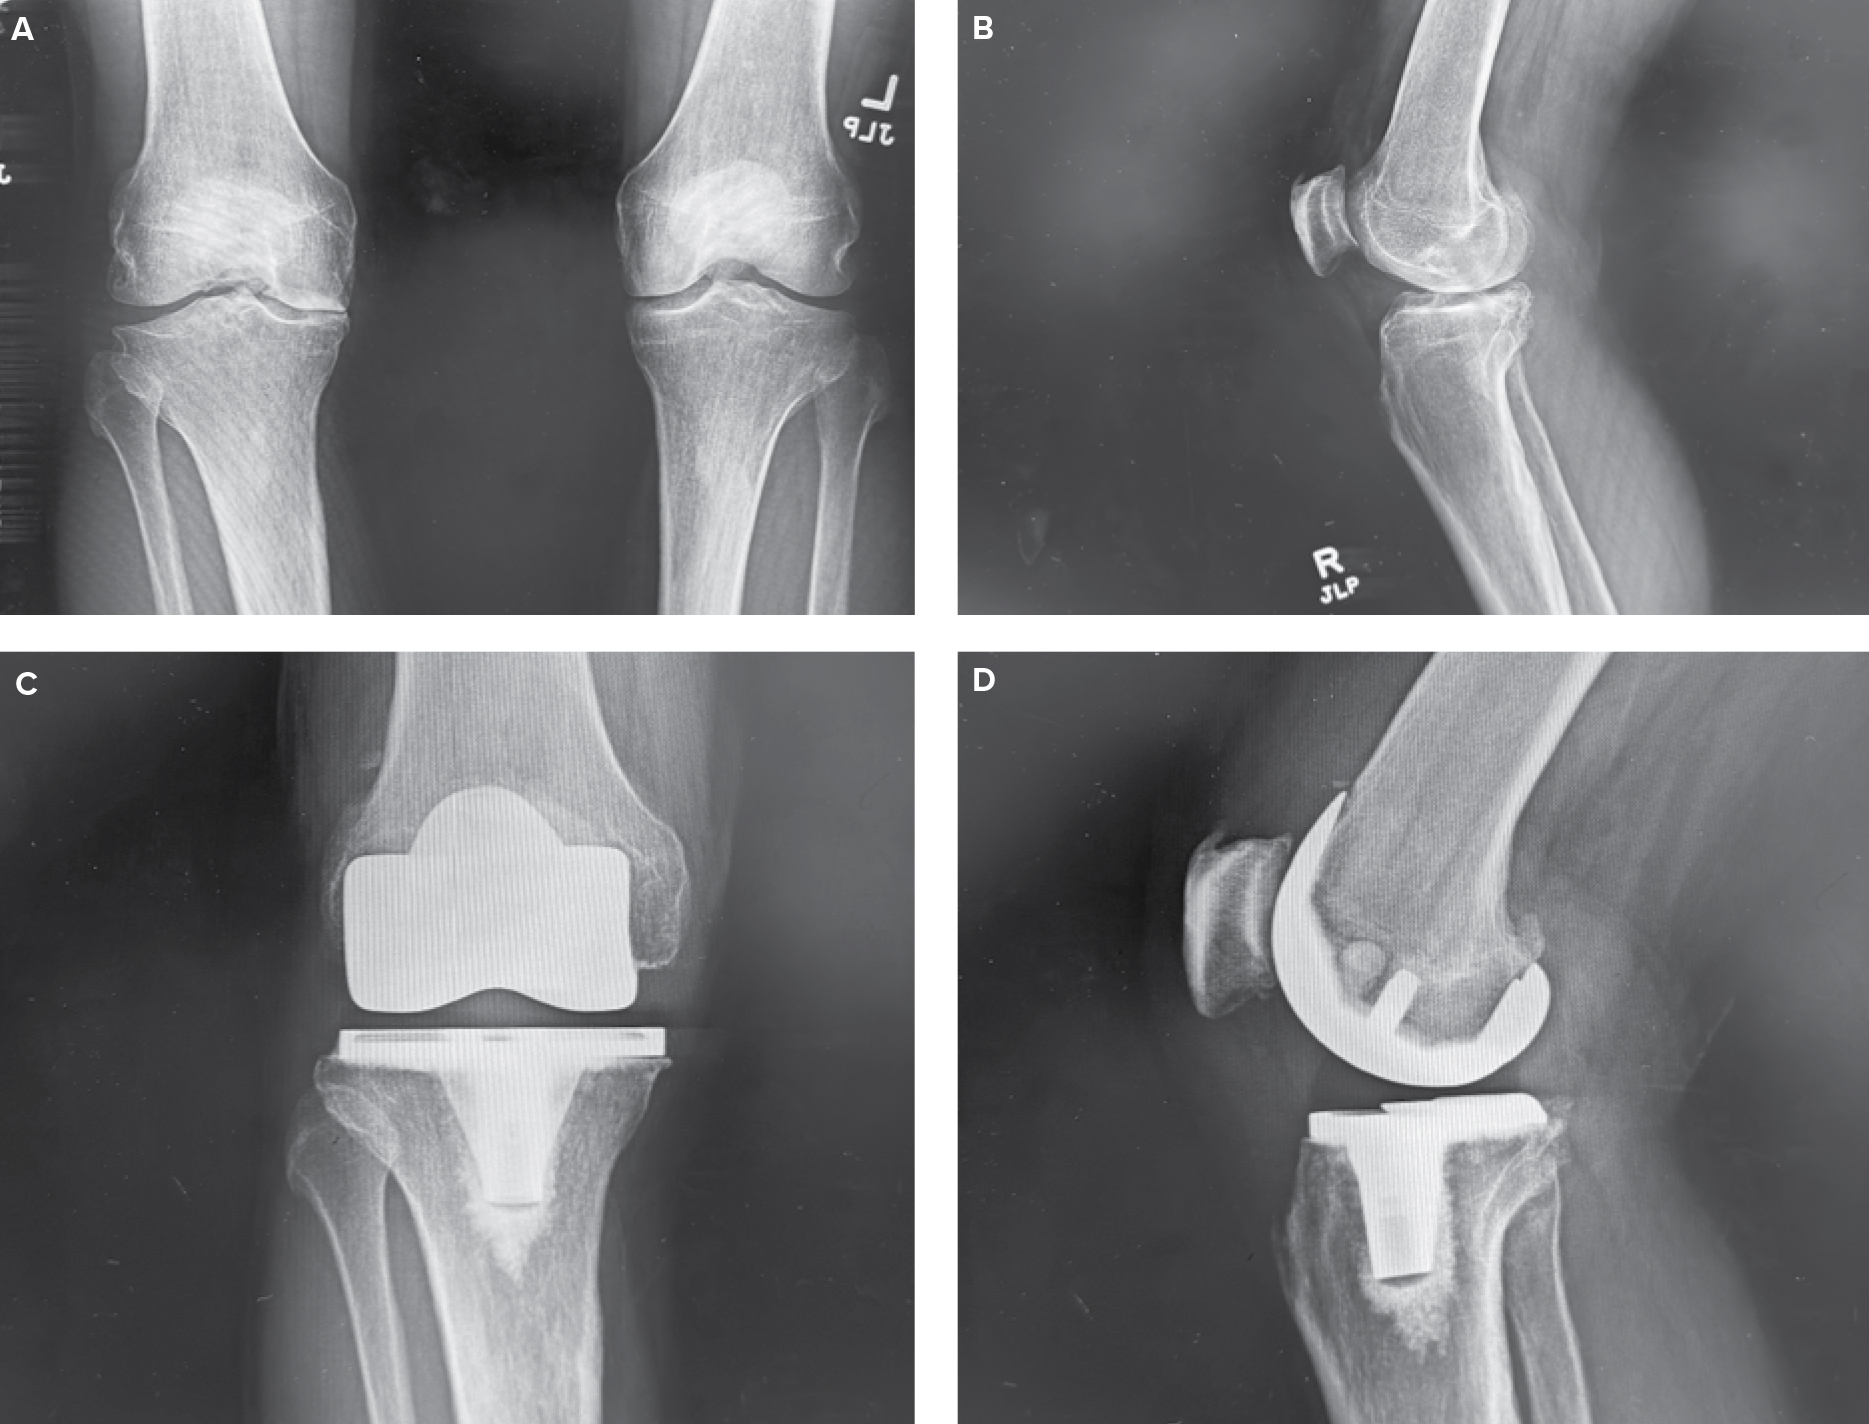

From www.researchgate.net

(A) Postoperative total knee arthroplasty (TKA) physical therapy (PT Apta Total Knee Replacement Cpg in total knee arthroplasty (tka), or total knee replacement, specific compartments of the knee joint are. a clinical practice guideline on total knee arthroplasty was developed by an american physical therapy (apta). teach importance of early mobility and appropriate progression of therapy. total knee arthroplasty (tka), also known as a total knee replacement, is an elective. Apta Total Knee Replacement Cpg.